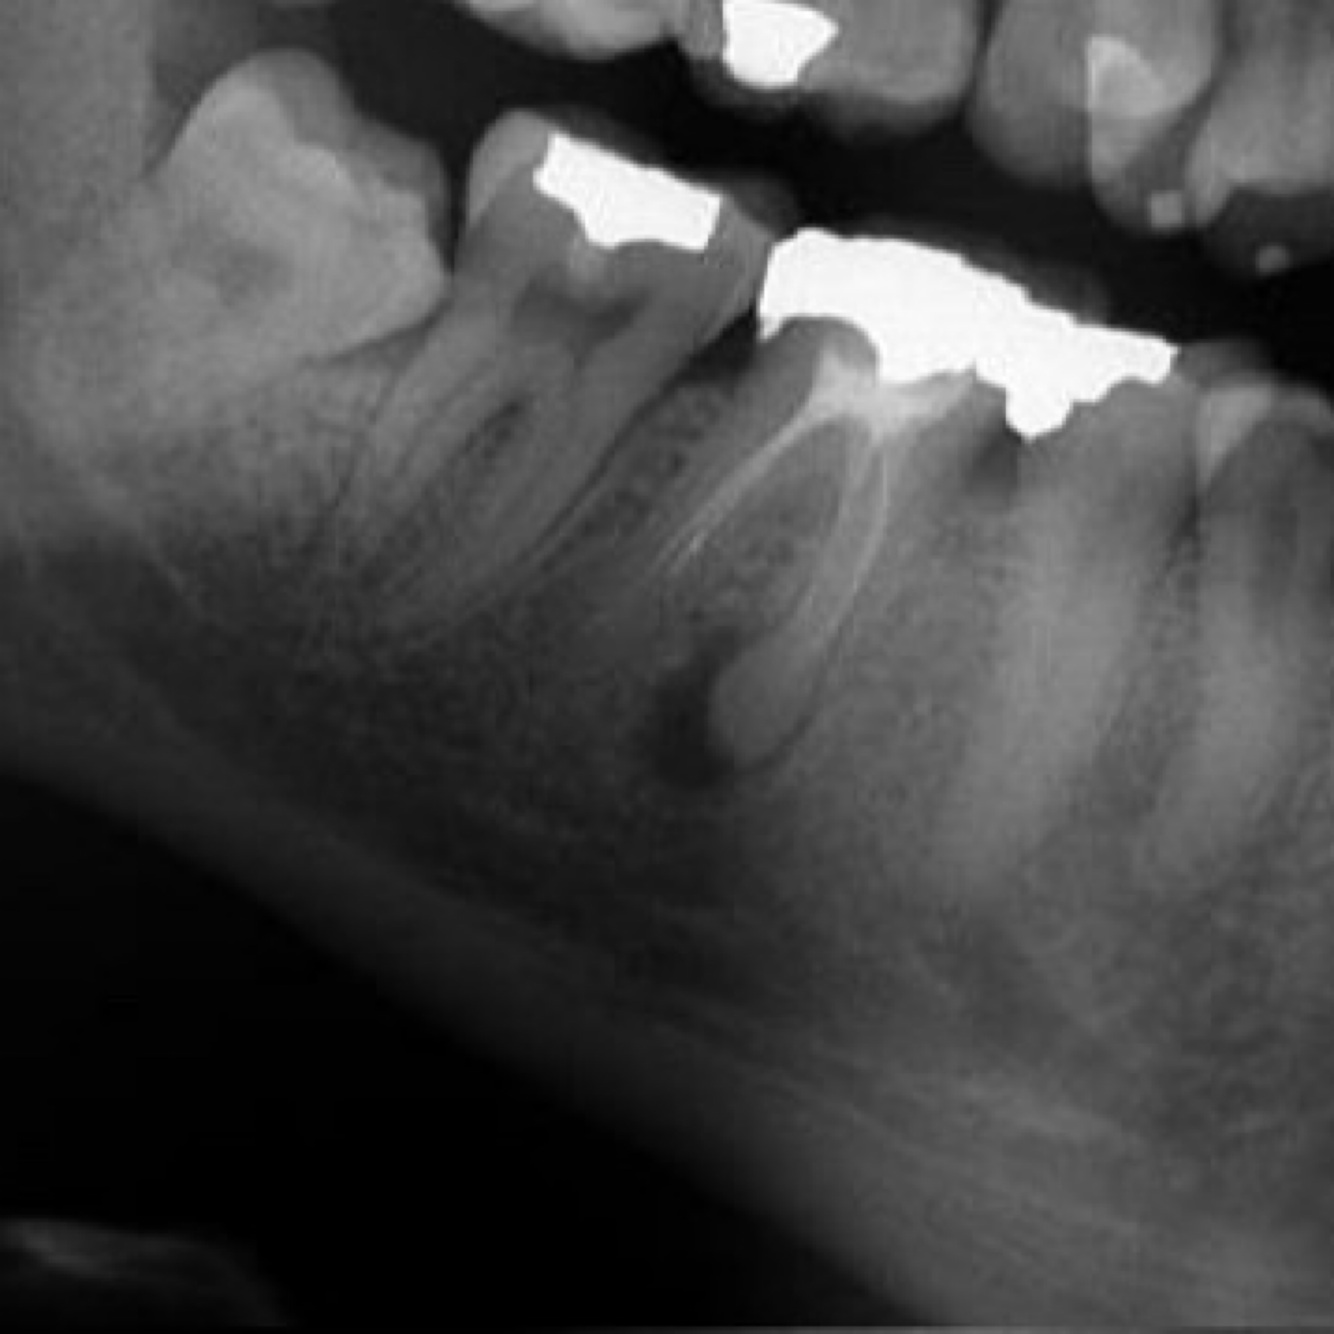

What is Cemento osseous dysplasia?

A

• often single lesion associated with apex of tooth

Florid cemento osseous dysplasia

- mutliple lesions at apex of teeth, often mandibular incisors

• swelling can extend into floor of mouth